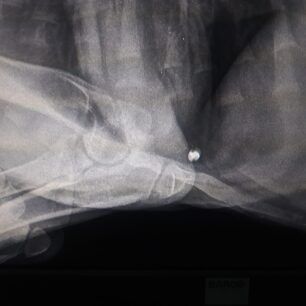

Στις ακτινογραφίες που διενεργήθηκαν ανευρέθηκε βλήμα αεροβόλου όπλου στη θωρακική κοιλότητα οπισθοστερνικά, έντονα ελαττωμένη οστική πυκνότητα ιδιαίτερα στα οπίσθια άκρα, αξιοσημείωτη χαλαρότητα αμφοτερόπλευρα και στα δύο γόνατα πού συνάδει με εικόνα ρήξεως πρόσθιου χιαστού. Στην ουσία όπως θα δείτε και στις ακτίνες μετά από ένα σημείο το στο σχεδόν παύει να υπάρχει, αν όχι από όταν γεννήθηκε τότε στην πορεία το ζώο όσο πιο ατρωφικο γινόταν το οστό τόσο τον οδηγούσε στην κατάσταση που είναι τώρα. Ο Αslan έχει 10% πιθανότητες όχι να περπατήσει αλλά να σταθεί, παρόλα αυτά δεν θα τα παρατήσουμε αφού έχει μια ζωντάνια και μια θέληση για ζωή που θαυμάζω μετά όλο αυτό που του συνέβη στους 5 μήνες της ζωής του ... Θα ακολουθήσουμε φαρμακευτική αγωγή για την θρέψη των οστών και σε 1 μήνα θα πρέπει να πάμε ξανά να δούμε πως πάμε! Για όποιον θέλει να βοηθήσει αυτοί είναι οι λογαριασμοί του κτηνιάτρου κ Νίκου πατσινακιδη.